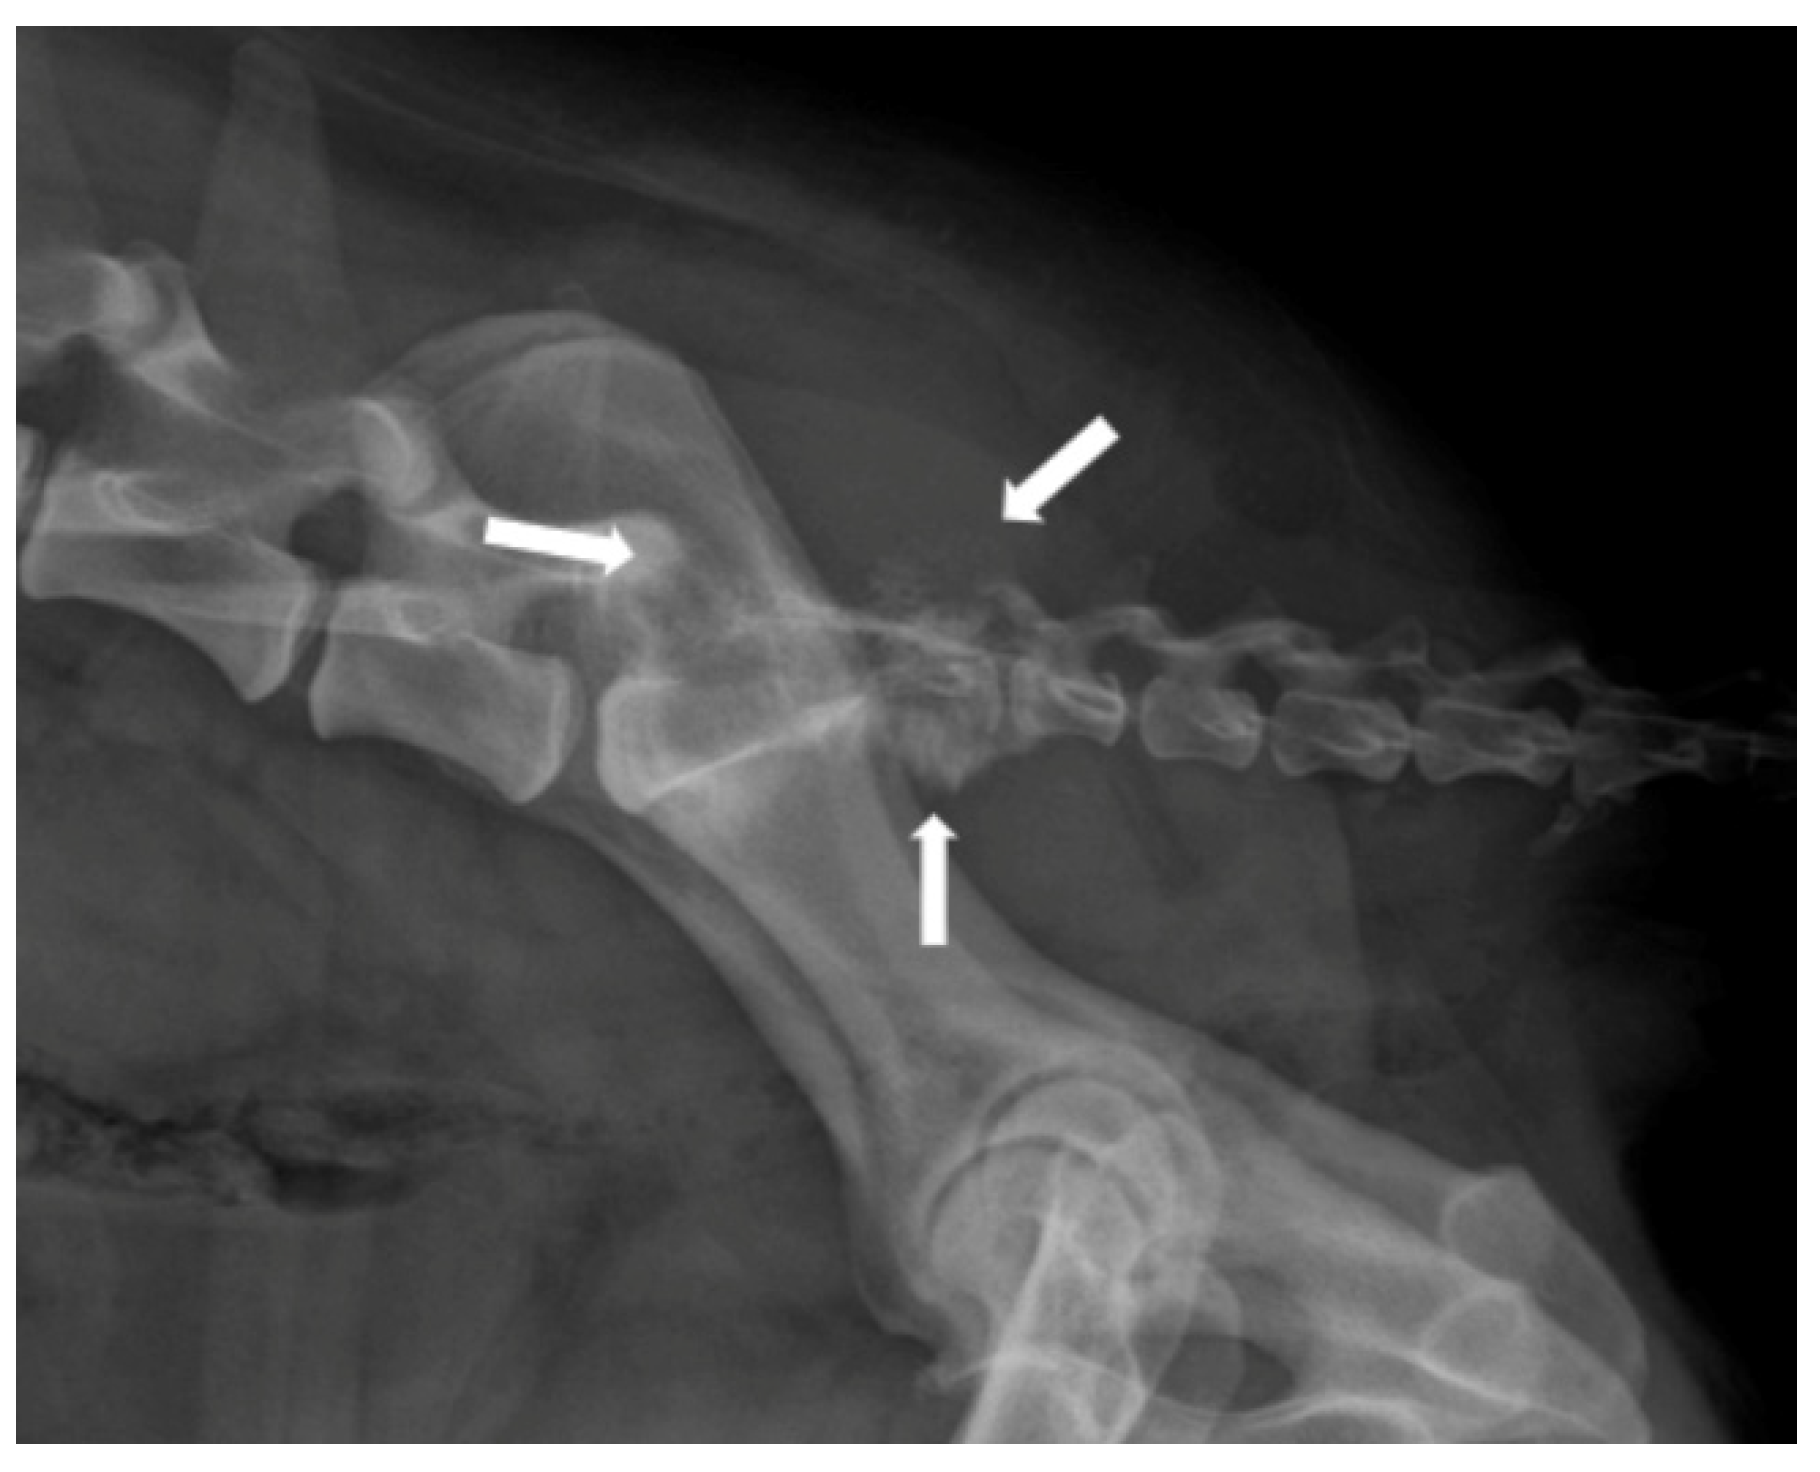

3.3. Spinal Cord Neoplasia

- Bagley, R.S. Spinal Neoplasms in Small Animals. Vet. Clin. N. Am. Small Anim. Pract. 2010, 40, 915–927. [Google Scholar] [CrossRef]

- Petersen, S.A.; Sturges, B.K.; Dickinson, P.J.; Pollard, R.E.; Kass, P.H.; Kent, M.; Vernau, K.M.; Lecouteur, R.A.; Higgins, R.J. Canine Intraspinal Meningiomas: Imaging Features, Histopathologic Classification, and Long-Term Outcome in 34 Dogs. J. Vet. Intern. Med. 2008, 22, 946–953. [Google Scholar] [CrossRef]

- Besalti, O.; Caliskan, M.; Can, P.; Vural, S.A.; Algin, O.; Ahlat, O. Imaging and Surgical Outcomes of Spinal Tumors in 18 Dogs and One Cat. J. Vet. Sci. 2016, 17, 225–234. [Google Scholar] [CrossRef]

- Auger, M.; Hecht, S.; Springer, C.M. Magnetic Resonance Imaging Features of Extradural Spinal Neoplasia in 60 Dogs and Seven Cats. Front. Vet. Sci. 2021, 7, 610490. [Google Scholar] [CrossRef] [PubMed]

- Tam, C.; Hecht, S.; Mai, W.; Nelson, N.; Chen, A.V.; Griffin IV, J.F. Cranial and Vertebral Osteosarcoma Commonly Has T2 Signal Heterogeneity, Contrast Enhancement, and Osteolysis on MRI: A Case Series of 35 Dogs. Vet. Radiol. Ultrasound 2022, 63, 552–562. [Google Scholar] [CrossRef]

- Lacassagne, K.; Hearon, K.; Berg, J.; Séguin, B.; Hoyt, L.; Byer, B.; Selmic, L.E. Canine Spinal Meningiomas and Nerve Sheath Tumours in 34 Dogs (2008–2016): Distribution and Long-Term Outcome Based upon Histopathology and Treatment Modality. Vet. Comp. Oncol. 2018, 16, 344–351. [Google Scholar] [CrossRef]

- Pancotto, T.E.; Rossmeisl, J.H., Jr.; Zimmerman, K.; Robertson, J.L.; Werre, S.R. Intramedullary Spinal Cord Neoplasia in 53 Dogs (1990–2010): Distribution, Clinicopathologic Characteristics, and Clinical Behavior. J. Vet. Intern. Med. 2013, 27, 1500–1508. [Google Scholar] [CrossRef]

- Luttgen, P.J. Neoplasms of the Spine. Vet. Clin. N. Am. Small Anim. Pract. 1992, 22, 973–984. [Google Scholar] [CrossRef]

- Krasnow, M.S.; Griffin, J.F.; Levine, J.M.; Mai, W.; Pancotto, T.E.; Kent, M.; Harcourt-Brown, T.R.; Carrera-Justiz, S.C.; Gilmour, L.J.; Masciarelli, A.E.; et al. Agreement and Differentiation of Intradural Spinal Cord Lesions in Dogs Using Magnetic Resonance Imaging. J. Vet. Intern. Med. 2022, 36, 171–178. [Google Scholar] [CrossRef]